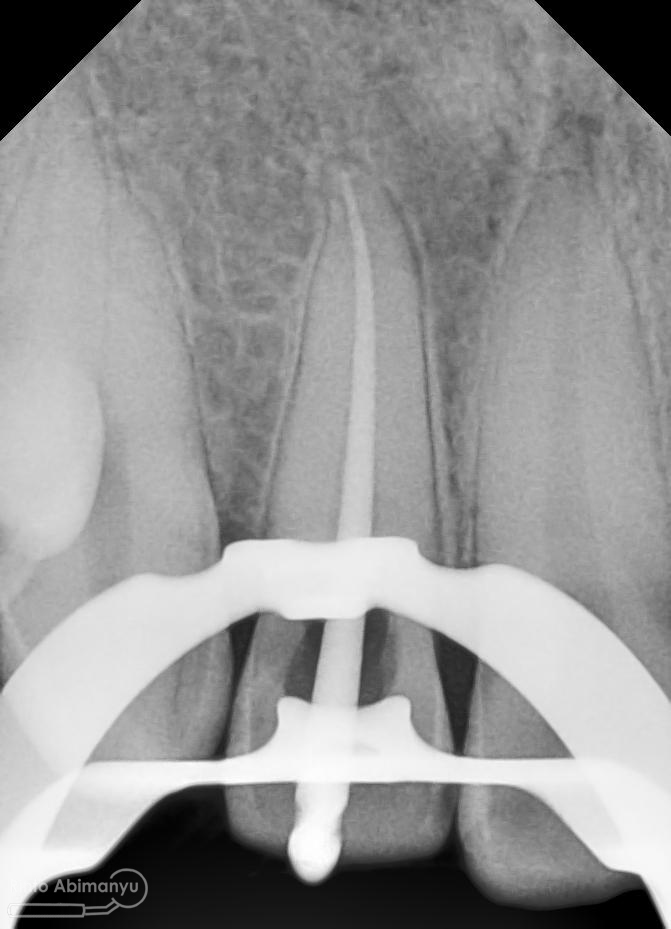

Oo iya tidak lupa juga dilakukan foto ronsen setelah pemasangan crown…

Foto radiografis akhir

Dari foto ronsen terlihat gambaran yang “indah” dari mulai pengisian saluran akar yang rapat dan padat serta gambaran sementasi mahkota yang terlihat homogen….

Nah dari foto ronsen ini juga saya melakukan evaluasi hasil pengisian pada gigi 11 21 nya… alhamdulillah pengisian yang kemarin terlihat sepanjang kerja dan padat serta rapat… Pada gigi 22 nya pun pengepasan guttap terlihat sudah sepanjang kerja…

Foto radiografis selesai perawatan saluran akar pada semua gigi